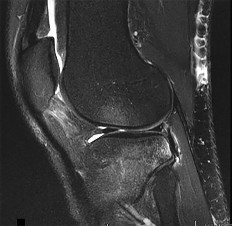

A 73-year-old man goes to the emergency department after tripping and falling down roughly thirteen steps at home. Prior to the injury, the patient had well-controlled medical comorbidities and was independent with all activities of daily living. Figures 1 through 3 show the injury sustained by the patient. What is the most appropriate definitive treatment for this patient?